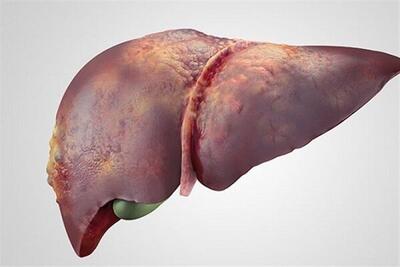

ویروس هپاتیت

ببینید | بیماری هپاتیت چیست؟

در این کلیپ با بیماری هپاتیت، انواع آن و علائم این بیماری آشنا میشوید.